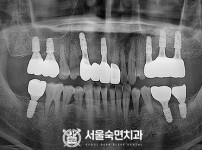

임플란트-전후사진2

치과를-선택할-때-꼭-확인하세요-서울숙면치과-임플란트-전후사진